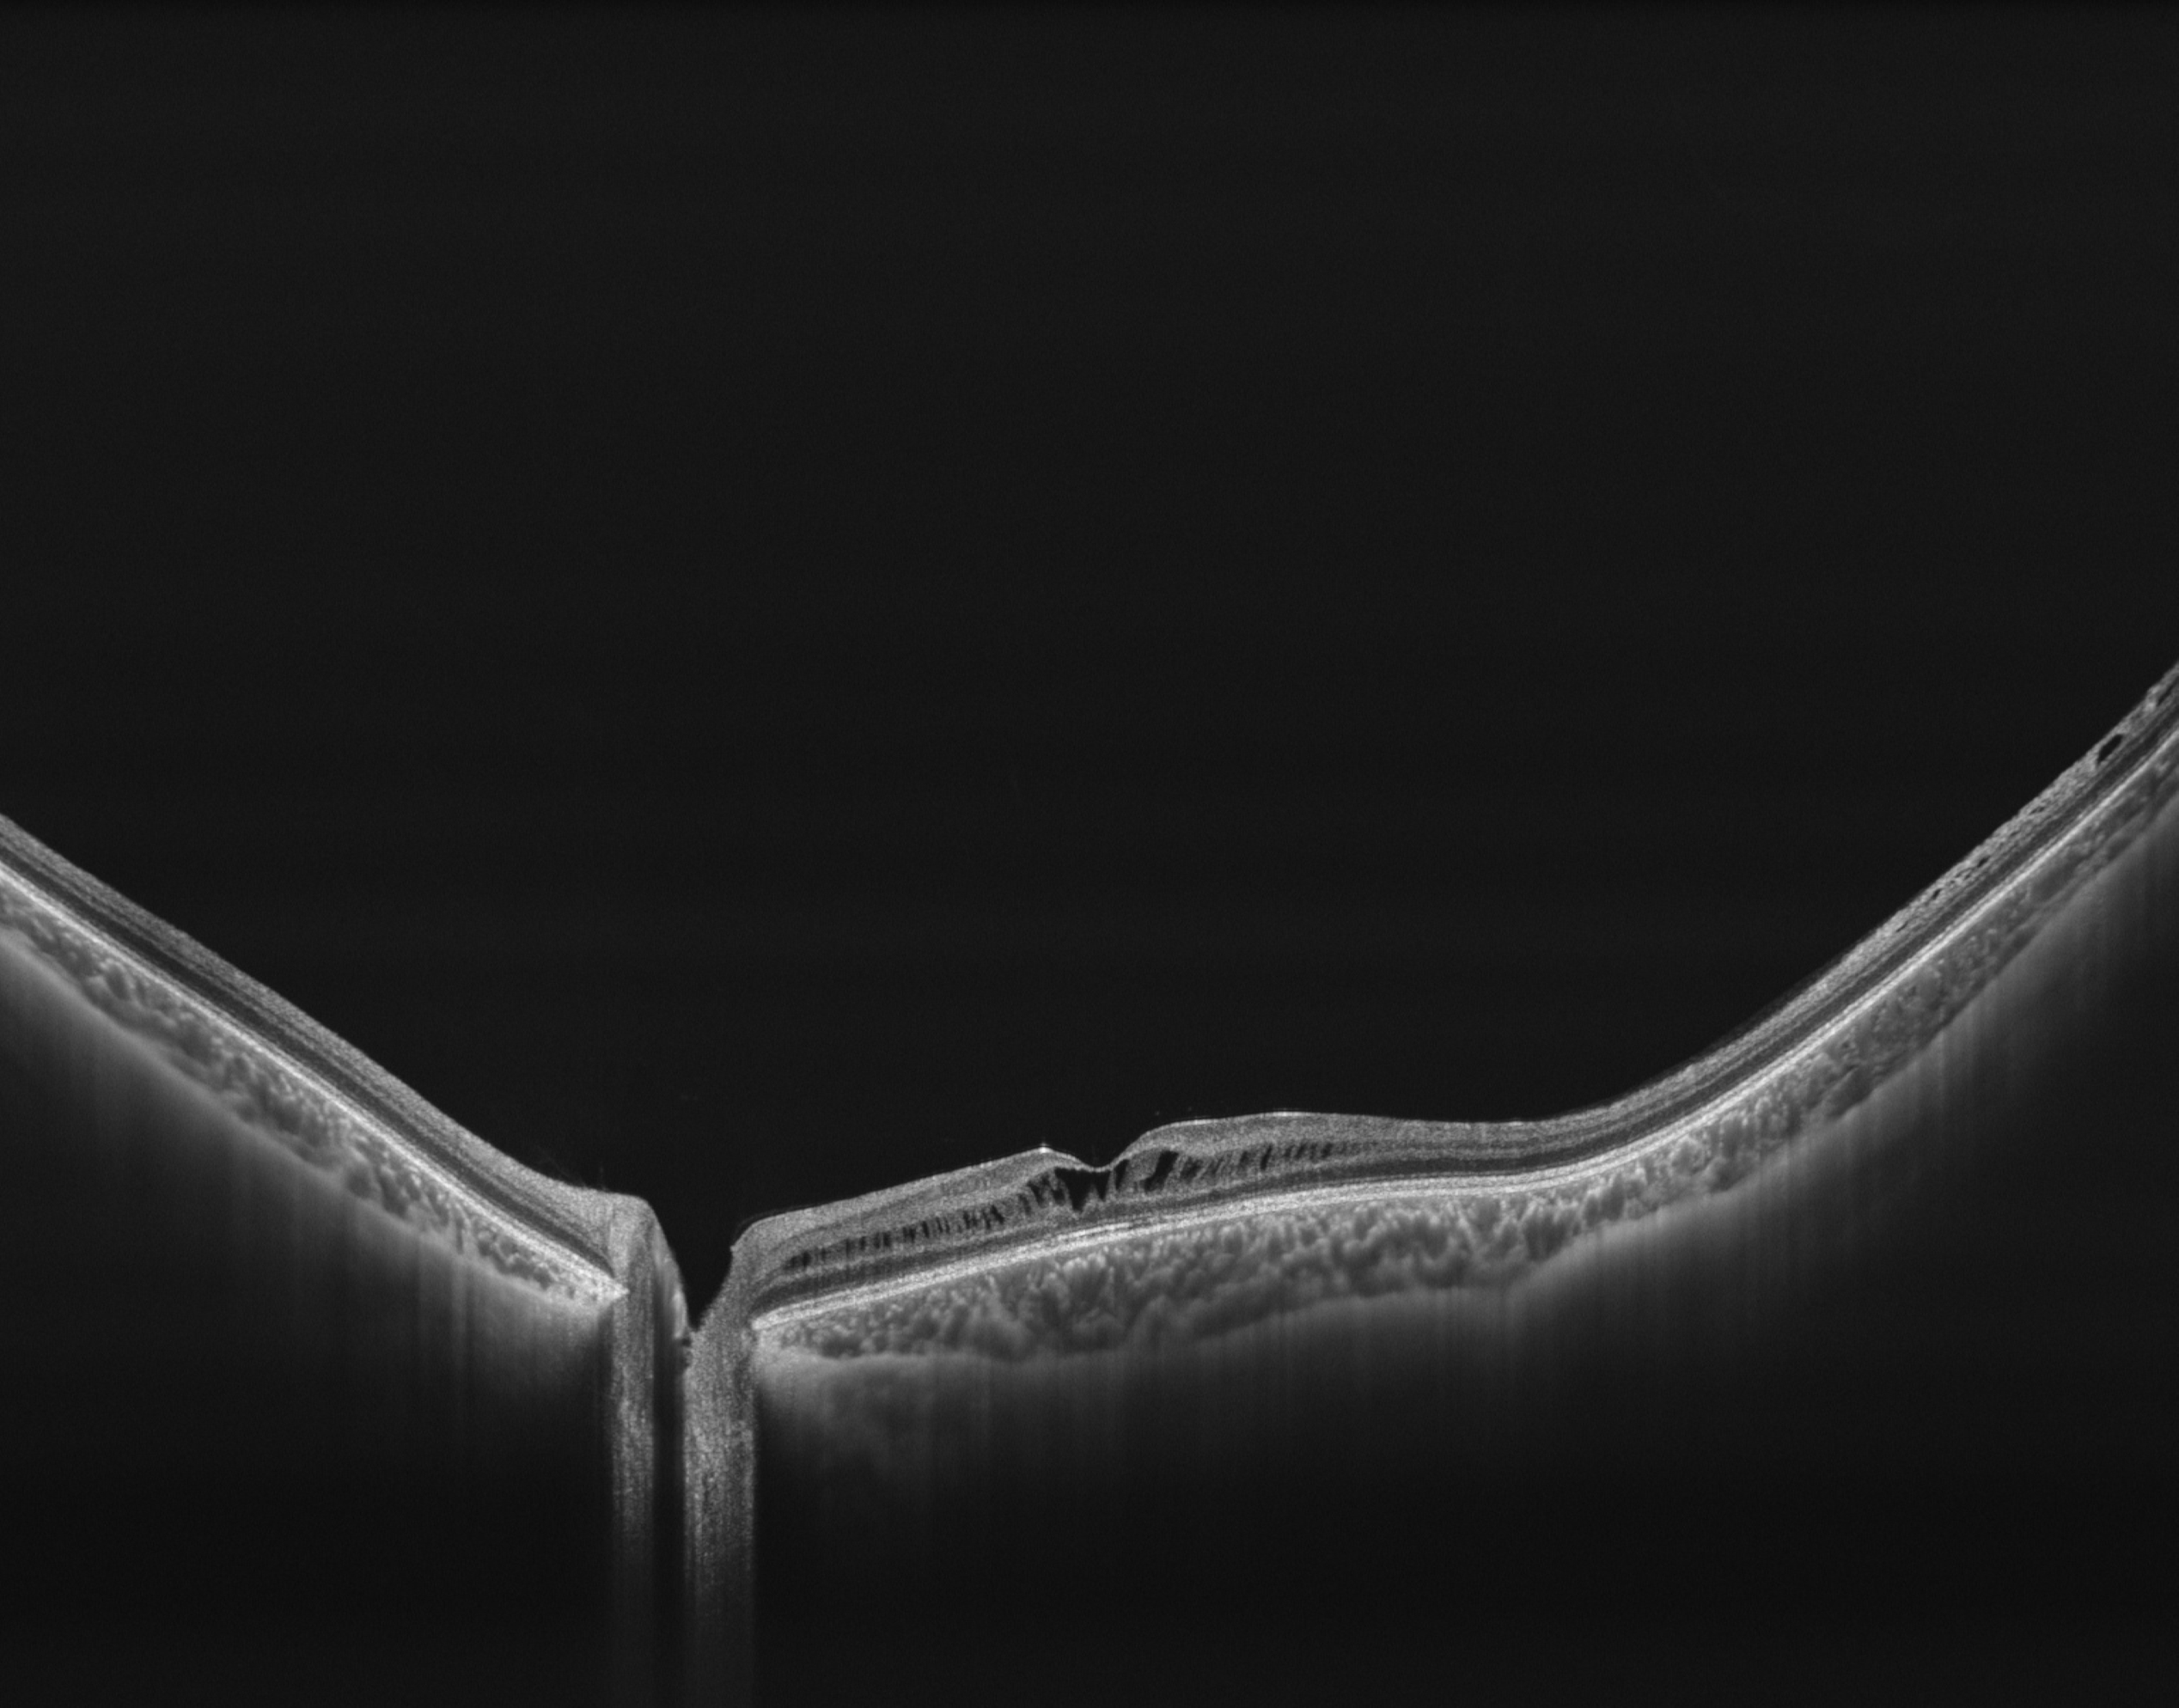

Full Range Retina OCT

- Van achterste glasvocht tot choroidea-sclera

- 24 mm tot 6 mm netvliesscan

- Automatische laagdetectie, segmentatie en meting van elke laag van het netvlies en choroïd

- 7×7 mm ganglion-macula-analyse meet de afstand van de interne begrenzingsmembraan (ILM) tot de buitenzijde van de binnenste plexiforme laag (IPL), die de binnenste 3 lagen van het netvlies vormt (NFL, ganglioncellagen, IPL), inclusief significantiemap (GMA-dikte vs. normatieve database)

- 15×9 mm 3D-scan voor iHealth-rapport met uitgebreide analyse van papil en macula